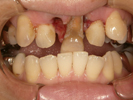

50代女性

治療前 |

治療中。仮歯。 左上の奥にインプラント埋入。 噛みあわせ治療を行いました |

治療後 全体の歯で食事がおいしくできるようになったと喜んでおられました。 |